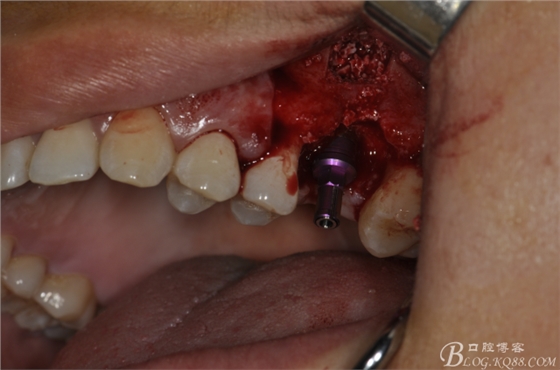

術(shù)中照片。

超聲骨刀切開骨外板 上頜竇外提一例